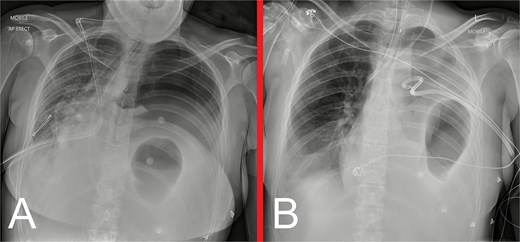

She remained well on outpatient follow-up at 2 weeks. Progress CXRs at 3 and 7 months showed satisfactory appearances, without evidence of hernia recurrence (Fig. 6).

Progress anteroposterior view CXRs taken at (A) 3 months and (B) 7 months postoperatively, showing persistent, but stable, left hemidiaphragm elevation with associated generalized volume loss of the left lung, but no evidence of hernia recurrence.